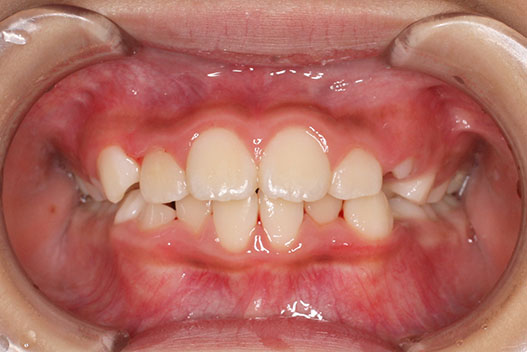

側方歯(犬歯、小臼歯)の生え変わりの時期。 前歯のがたつきを気にされ、小児矯正からの治療を希望されました。 お母様は、矯正治療経験済みですので、治療には前向きで早期治療の必要性を納得されていました。 小児矯正では、永久歯の生え変わるためのスペースを増加させ、がたつきを軽減させることを目的で行います。 残ったがたつきは、全ての永久歯が生え変わってから、本格矯正(マルチブラケット装置での治療)で改善しています。 比較的、叢生量は少ないため、本格矯正は非抜歯にて配列しました。

マルチブラケット 動的治療期間 2年6か月 調整回数16回 特に問題もなく、保定後も安定しています。